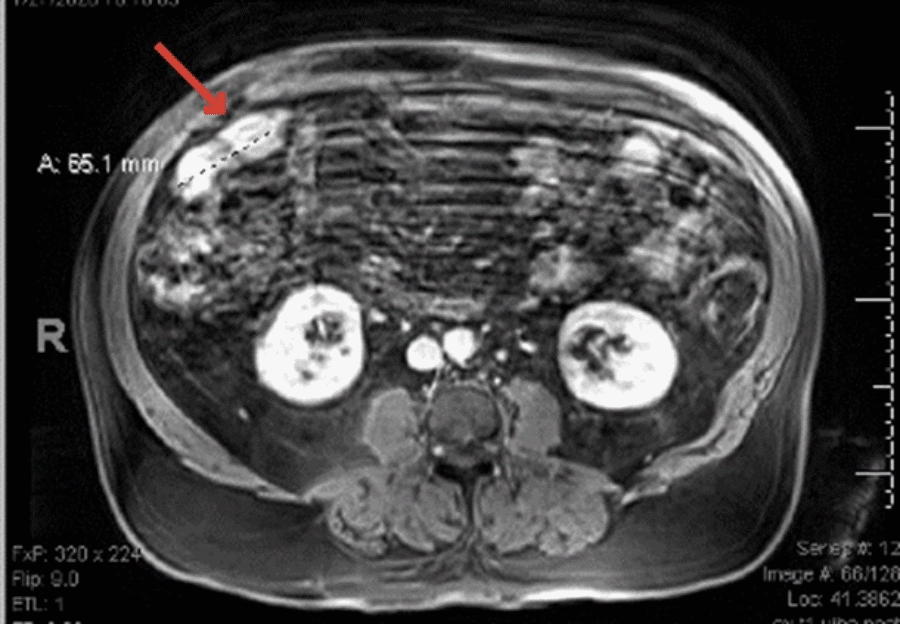

Further investigation identified that the patient had an esophagogastroduodenoscopy (EGD) just prior to this incident for longstanding reflux. The EGD showed multiple gastric antral ulcers and grade B esophagitis with no evidence of bleeding. He then underwent a colonoscopy for his anemia workup, which showed scattered sigmoid diverticula. A capsule endoscopy, performed to evaluate for distal small intestine pathology, demonstrated a friable polypoid lesion in the mid-distal ileum. To further characterize the mass, he had a magnetic resonance enterography scan (MRE), which showed abnormal thickening and enhancement of a 6.5 cm segment of the mid-distal ileum with no small bowel distention or lymphadenopathy (Figure 1). The patient was referred to our colorectal surgery department for surgical resection.

Figure 1. Magnetic Resonance Enterography Showing Mid-Distal Ileum Enhancement (arrow). Published with Permission